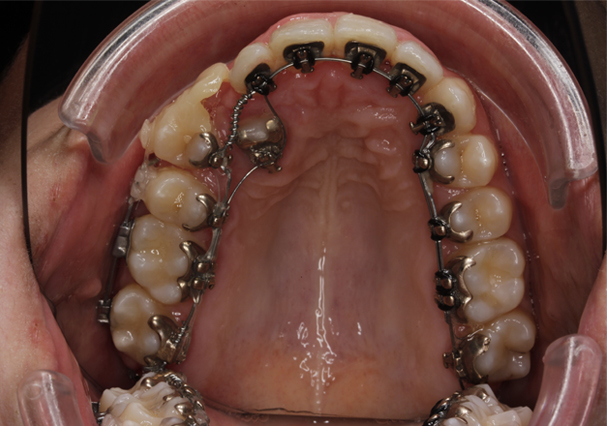

Tipo de ortodoncia

Ortodoncia lingual